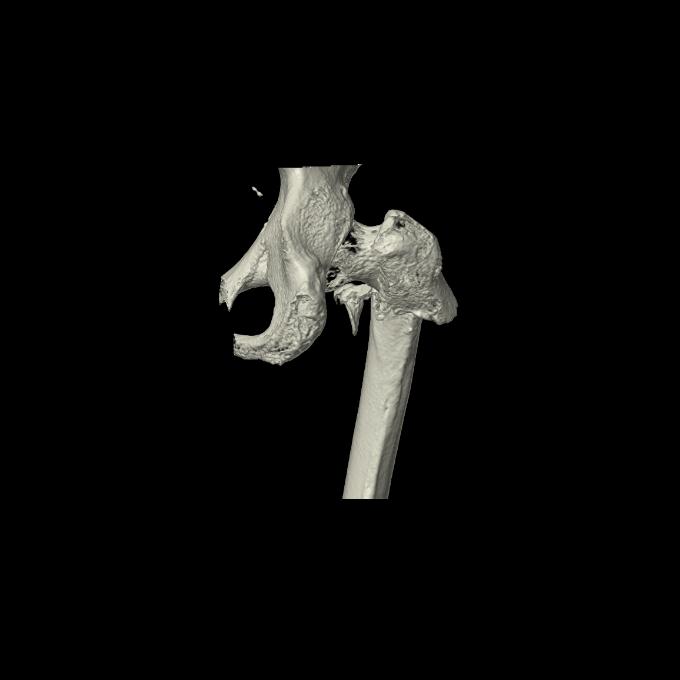

91569 3/25 両股正面とラウエン 70歳女性 人工骨頭+バンクーバー